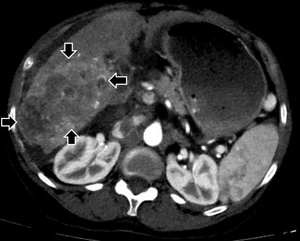

A CT of the liver showed a 10 x 6 cm-sized right hepatic mass demonstrating arterial hypervascularity and venous washout features of HCC with a few satellite masses in the setting of cirrhosis (Figure 1A). A right main portal vein tumor thrombus was also seen (Figure 1B).